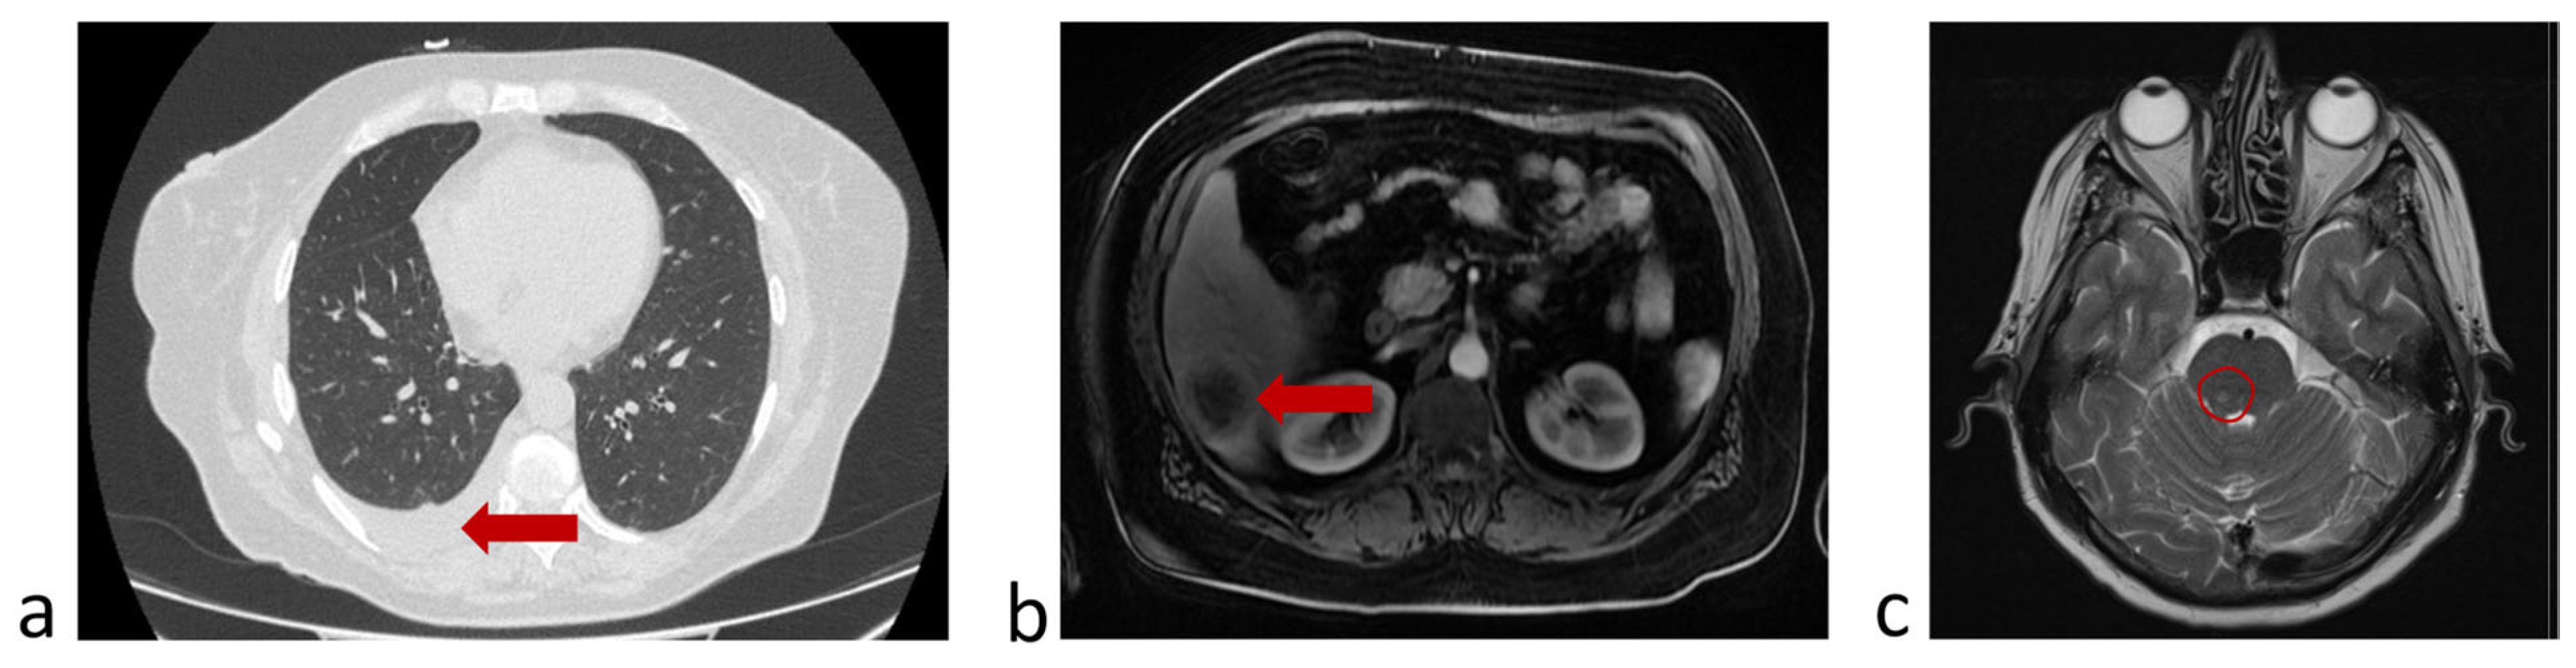

3.6.1. A Clinical Example Demonstrating a Favorable Outcome of the Disease and the Evolution of the Number of CTCs Detected in the Peripheral Blood